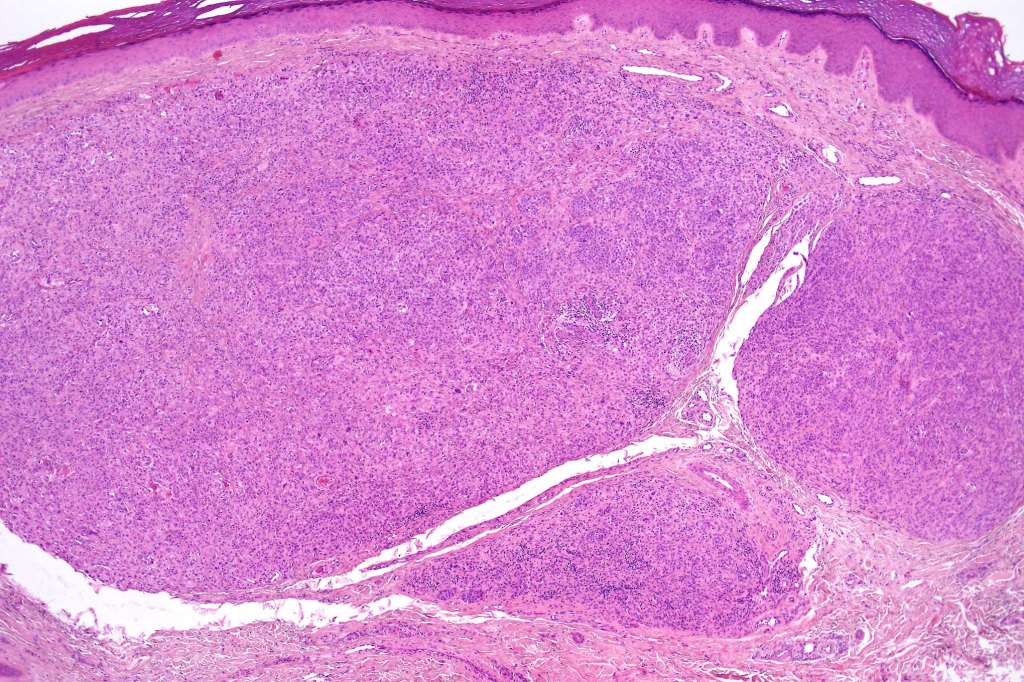

•May be a pure population (rare) or biphasic in association with banal or congenital nevus-like component

•Lymphocytic infiltrate

•Large epithelioid (sometimes Spitzoid or rhabdoid) cells with ground-glass cytoplasm

•Nuclear pseudoinclusions

•Few mitoses & variable pleomorphism